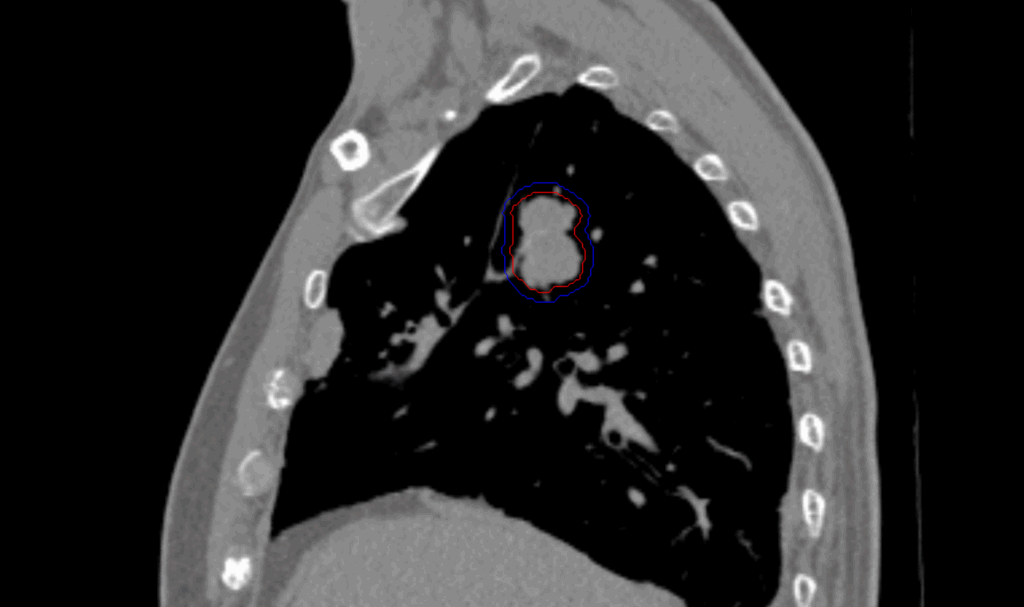

Planning CT Images